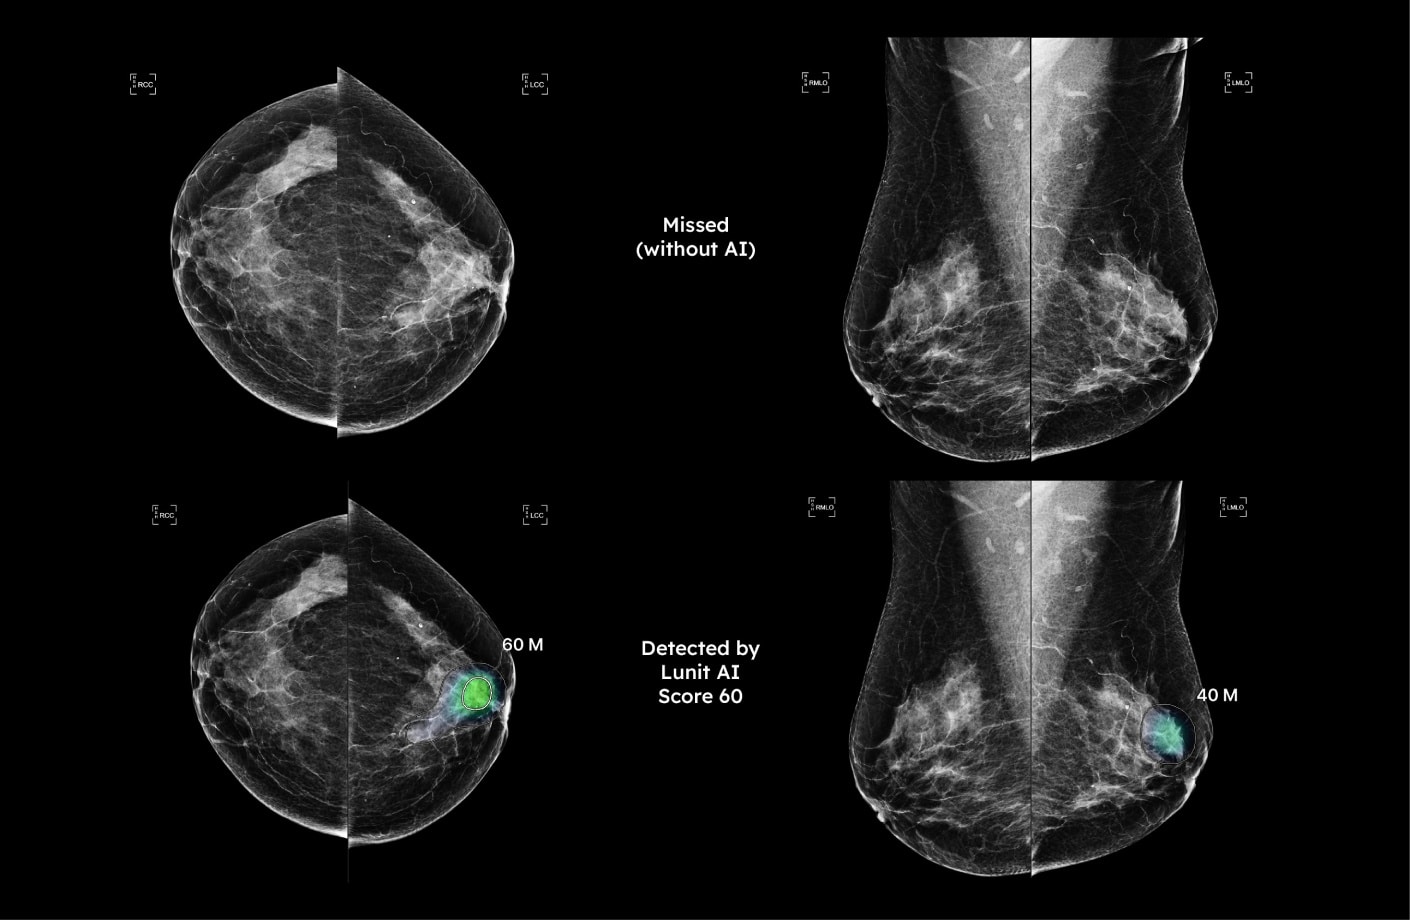

In a retrospective analysis, Lunit INSIGHT MMG correctly identified suspicious findings in a mammogram from 2020 that was originally overlooked. The patient was not diagnosed until 2022—highlighting the potential of AI mammogram reading tools to support earlier diagnosis.